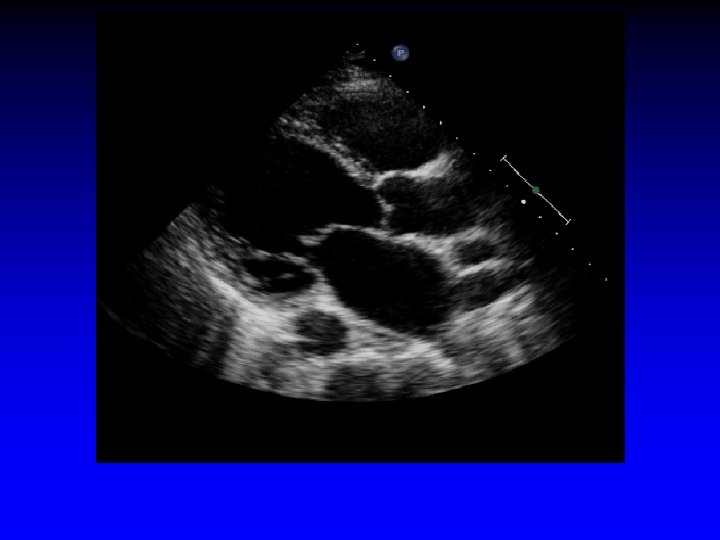

Case 7 Ischemic MR restricted PML

LVIDd = 6. 4 cm Dilated LV; posterior wall thinner than septum